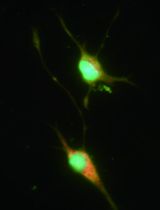

Amyloid-β (Aβ)-containing plaques accumulate in the brains of patients with Alzheimer’s disease (AD). Studies in transgenic mice which over-express amyloid precursor protein and presenilin 1 (APP/PS1 mice) have suggested that T cells that infiltrate the brain may influence the development of Aβ plaques and associated cognitive dysfuncation. Active immunization with Aβ peptides and adjuvants has been evaluated as a therapy for AD, based on the premise that it induces Aβ-specific antibodies that may help to clear the Aβ plaques. However, immunization with Aβ peptides and adjuvants also promotes the development of Aβ-specific T cells (McQuillan et al., 2010) and there is evidence that Aβ-specific T cell may influence the development of Aβ plaques and disease progression in AD patients. In the mouse model, Aβ-specific T cells that secrete IFN-γ (Th1 cells) have been shown to enhance the plaque burden (Browne et al., 2013). Adoptive transfer of Aβ-specific T cells that have been polarized in vitro to Th1, Th2, Th17 or Treg cells can be used to examine the function of these cells in vivo.